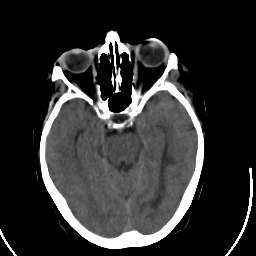

Stroke CT #2 -- Slice #9

[Home][Help][Clinical] Slice 9